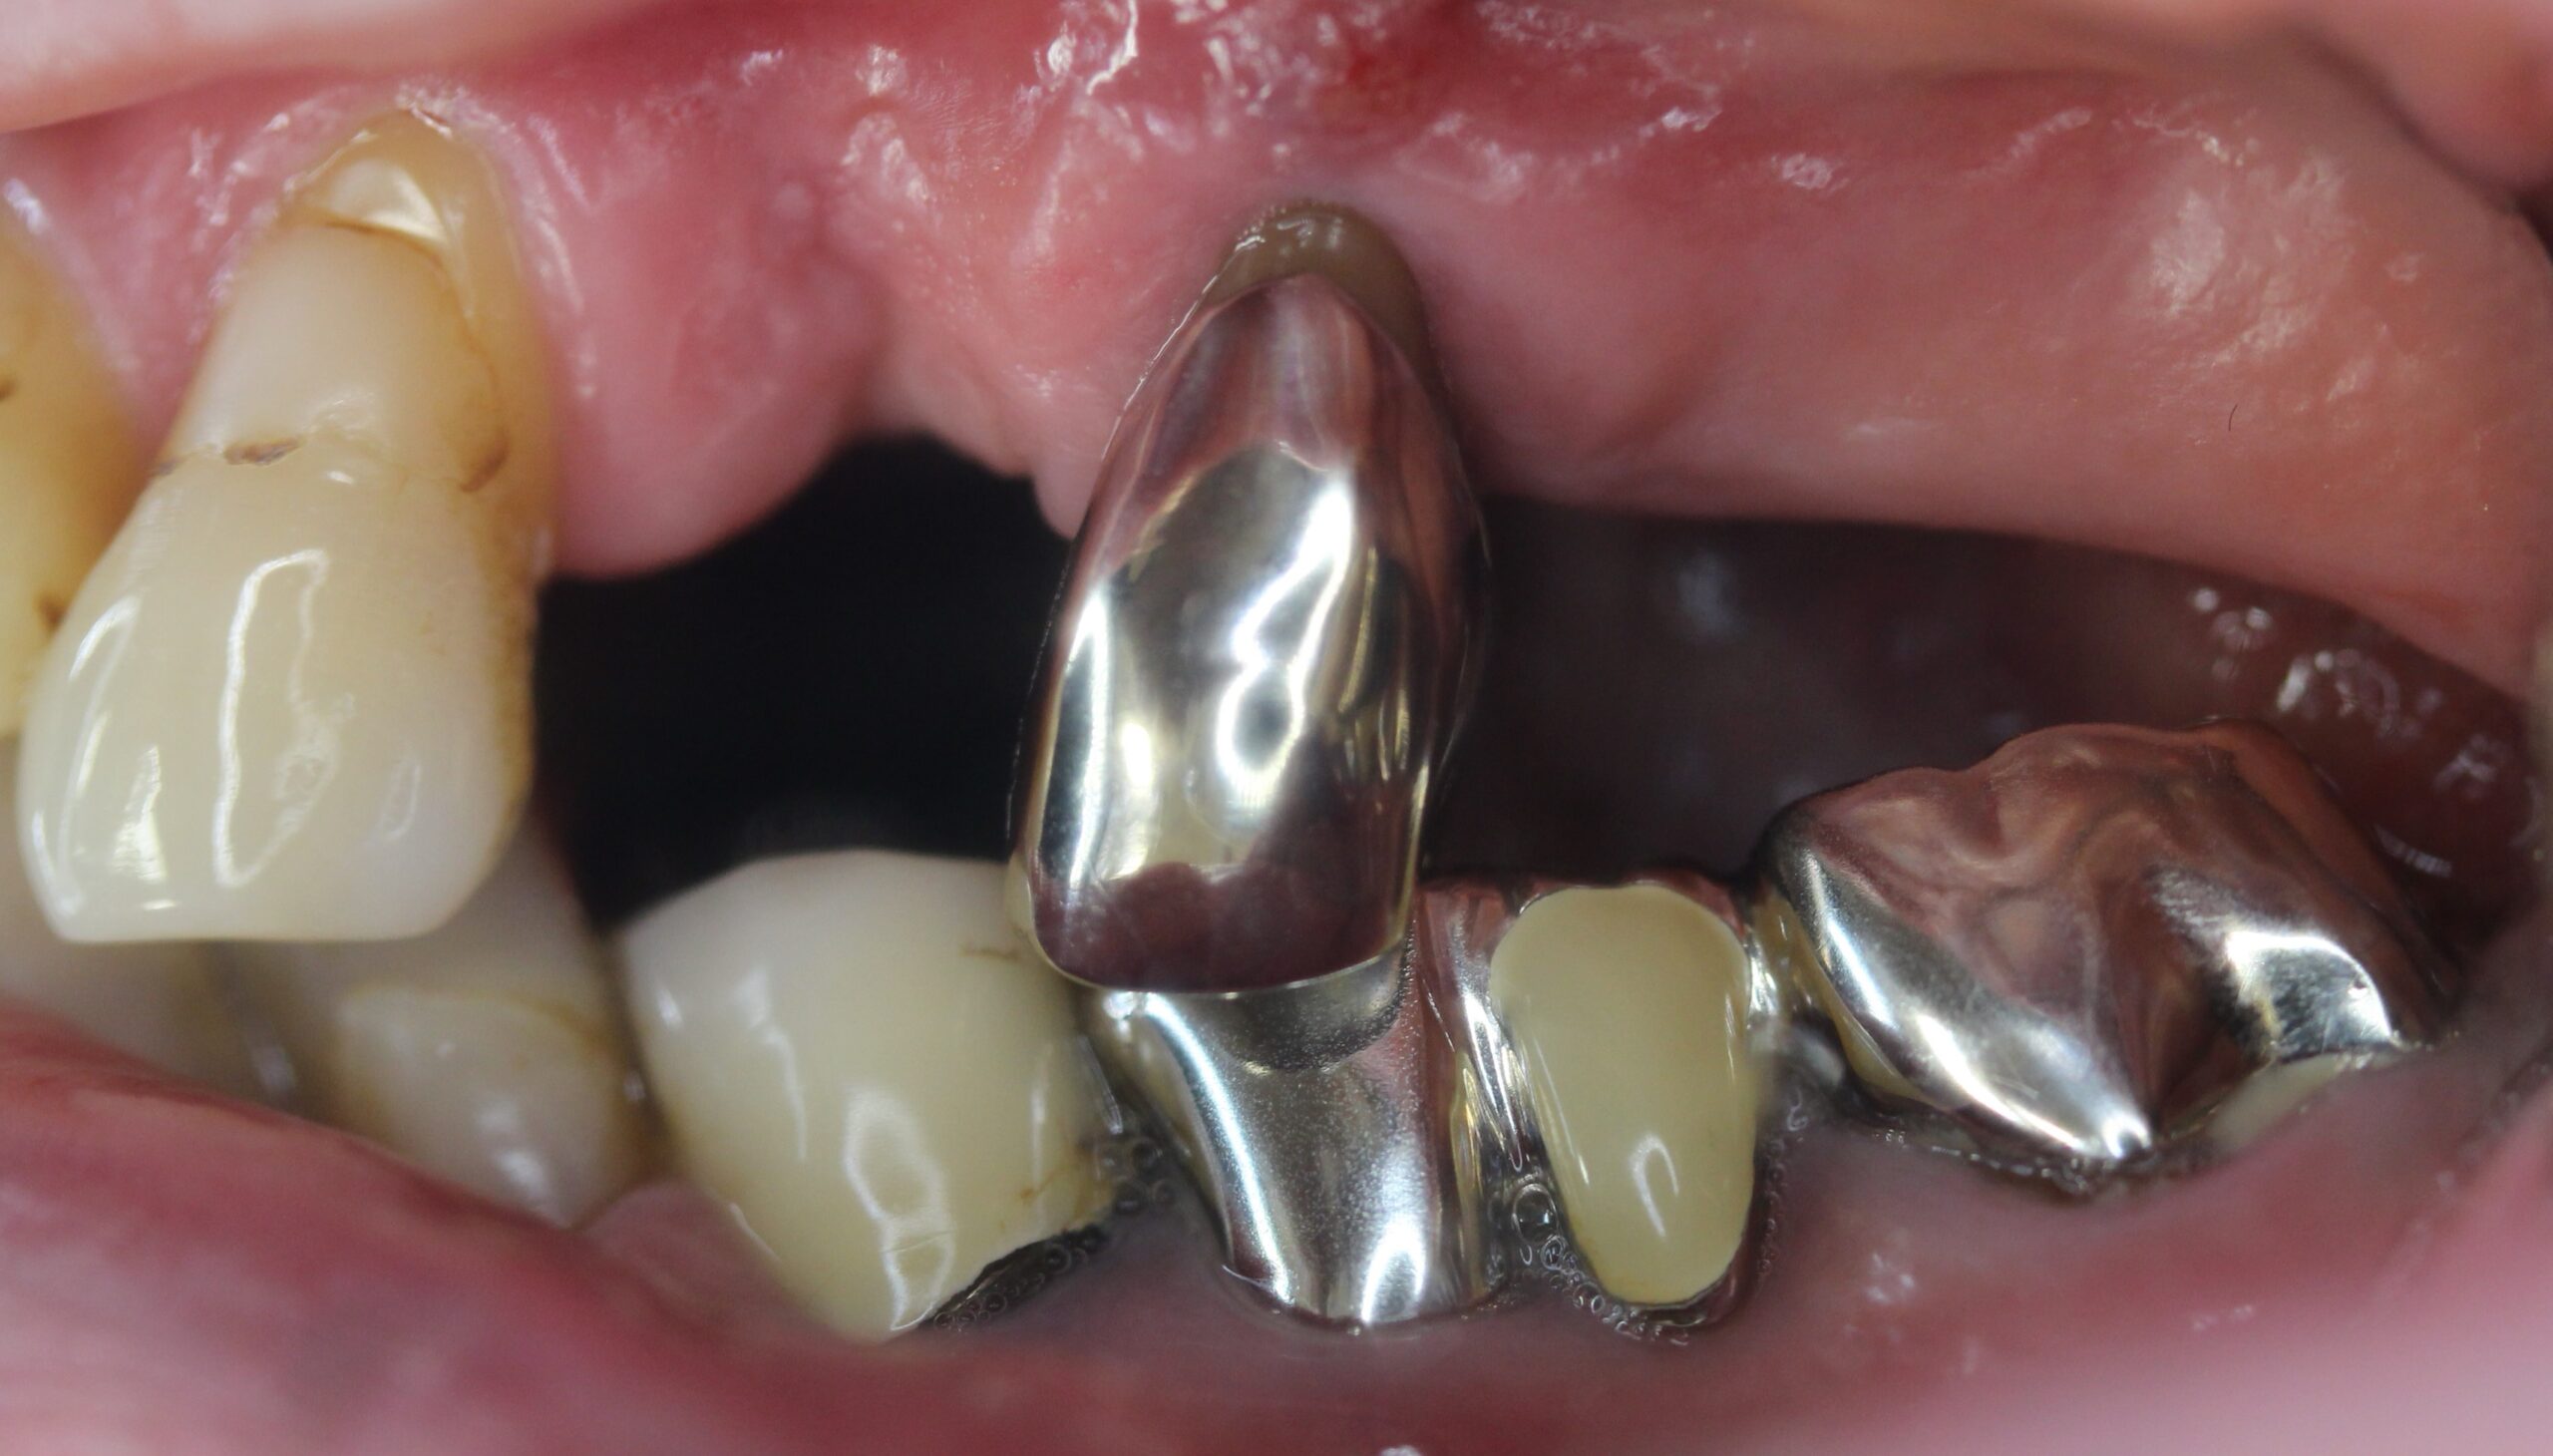

60代女性。歯がぐらついて噛めないので入れ歯を作り直したい。

入れ歯でちゃんと噛めないので新しく作り直したい。

上顎はコーヌステレスコープ、下顎はレジリエンツテレスコープにて治療を行なった。

【治療後】